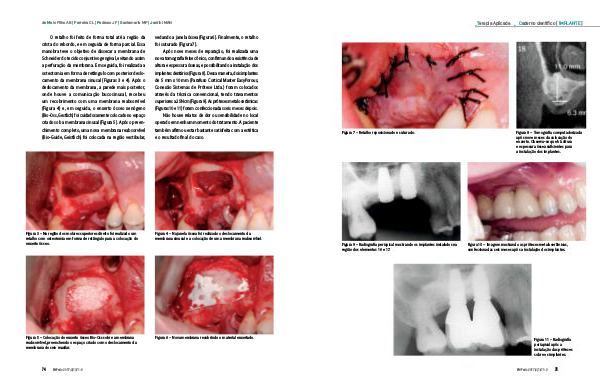

O retalho foi feito de forma total até a região da crista do rebordo, e em seguida de forma parcial. Essa manobra teve o objetivo de dissecar a membrana de Schneider do tecido conjuntivo gengival, evitando assim a perfuração da membrana. Em seguida, foi realizada a osteotomia em forma de retângulo com posterior deslocamento da membrana sinusal( Figuras 3 e 4). Após o deslocamento da membrana, a parede mais posterior, onde houve a comunicação bucosinusal, recebeu um recobrimento com uma membrana reabsorvível( Figura 4) e, em seguida, o enxerto ósseo xenógeno( Bio-Oss, Gestlich) foi cuidadosamente colocado no espaço criado sob a membrana sinusal( Figura 5). Após o preenchimento completo, uma nova membrana reabsorvível( Bio-Guide, Geistlich) foi colocada na região vestibular,

vedando a janela óssea( Figura 6). Finalmente, o retalho foi suturado( Figura 7).

Após nove meses de reparação, foi realizada uma nova tomografia feixe cônico, confirmando a existência de altura e espessura ósseas, e possibilitando a instalação dos implantes dentários( Figura 8). Dessa maneira, dois implantes de 5 mm x 10 mm( Parafuso Cortical Master EasyPorous, Conexão Sistemas de Prótese Ltda.) foram colocados através da técnica convencional, tendo travamentos superiores a 25 Ncm( Figura 9). As próteses metalocerâmicas( Figuras 10 e 11) foram confeccionadas seis meses depois.

Figura 3 – Na região dos molares superiores direito foi realizado um retalho com osteotomia em forma de retângulo para a colocação do enxerto ósseo.

Figura 4 – Na janela óssea foi realizado o deslocamento da membrana sinusal e a colocação de uma membrana reabsorvível.

Figura 5 – Colocação do enxerto ósseo Bio-Oss sobre a membrana reabsorvível, preenchendo o espaço criado com o deslocamento da membrana do seio maxilar.

Figura 6 – Nova membrana recobrindo o material enxertado.